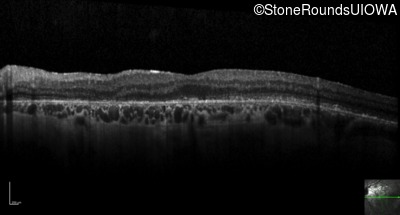

Optical Coherence Tomography - Left - 20/200

Exemplar / OCT Stack